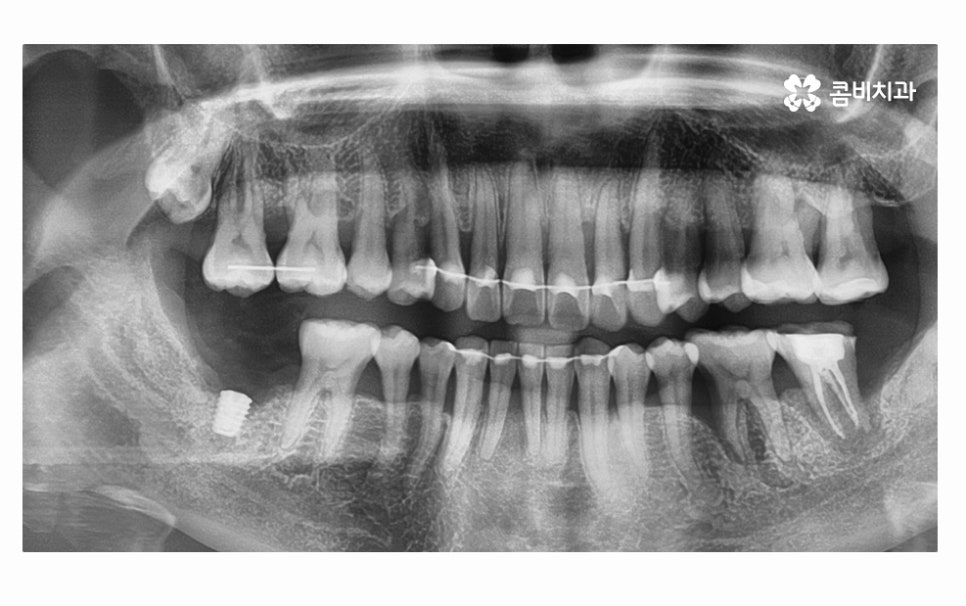

오늘 소개드릴 환자분의 케이스는 치아 상실의 요인이

잇몸질환이 심해져서 치아 뿌리까지 염증이 발생되었고

결국 어금니 발치 까지 이어진 사례라고 할 수 있는데요.

사진에서 보시는 것처럼 치아 사이에 빈 공간도 많고

잇몸이 내려앉아서 치아의 하단부도 많이 드러난 상태인데

치아를 잇몸이 제대로 감싸주지 못하고 이렇게

내려앉게 될 경우 치아도 많이 시리게 되고

치주염이 심해지는 단계에서는 치아가 흔들려서

식사도 제대로 하지 못할 정도로 어려움을 겪게 되실 수 있어요.